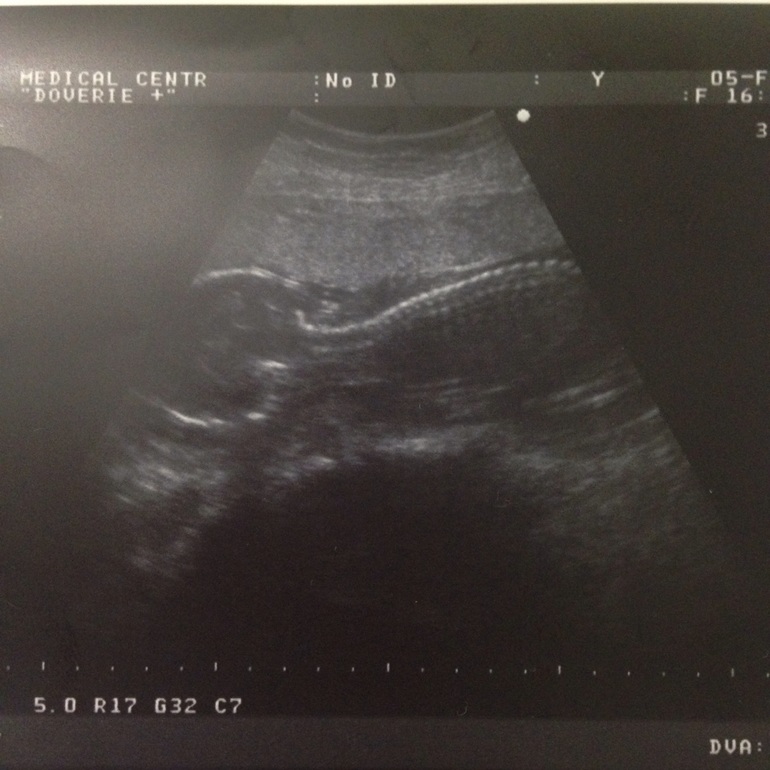

Вчера были на УЗИ )))

У нас мальчик!!!!